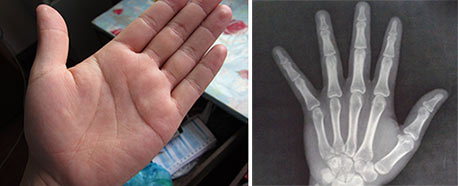

(图:患者到院时病情已经很严重,皮下出现痛风结节)

(图:曹先生痛风病情治疗,痛风石清除,手指关节恢复正常)